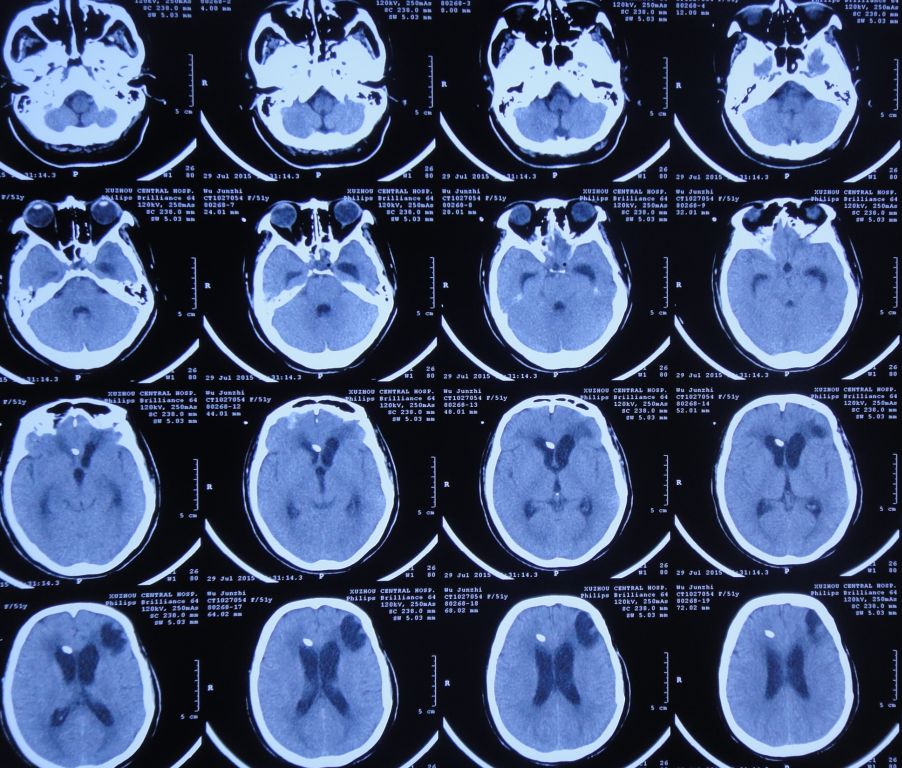

2015年7月27日患者突发高热,体温高达39.0 ℃,伴呕吐,意识转差,腰椎穿刺颅内压力极高,并留取脑脊液进行细菌培养;复查头CT检查显示脑室系统显著扩张,颅内积气(图11)。当日急诊进行了右侧侧脑室钻孔引流术,术后入住ICU给予重症监护、抗炎、抑酸等治疗。

图11:2015年7月27日头CT:脑室系统显著扩张,颅内积气

脑室引流术后第2天即2015年7月29日,患者神志恢复清楚,但仍有发热;复查头CT:脑室引流术后,脑室较前缩小(图12)。2天前腰穿留取的脑脊液细菌培养结果为白色假丝酵母菌,对氟康唑敏感,给予抗炎、抗真菌治疗。

图12:2015年7月29日头CT:脑室引流术后,脑室较前缩小

脑室引流术后第5天即2015年8月1日,患者体温恢复至正常,复查头CT:脑室扩张程度较引流术后减小(图13)。

图13:2015年8月1日头CT:脑室引流术后,脑室轻度扩张

拔除头部侧脑室外引流管后第2天即2015年8月3日,患者仍有脑脊液鼻漏,再次出现发热、头痛症状;复查头CT:脑室较前扩张,室旁水肿明显,颅内积气(图14),医生给予甘露醇脱水治疗。

图14:2015年8月3日头CT:脑室较前扩张,室旁水肿明显,颅内积气

2015年8月6日,复查头CT:脑室显著扩张,室旁水肿明显,颅内积气(图15)。患者仍有脑脊液鼻漏,但当地医院不予脑脊液漏修补治疗。

图15:2015年8月6日头CT:脑室显著扩张,室旁水肿明显,颅内积气

入院后第1天即2015年8月8日,复查头CT头:脑脊液蝶窦瘘征象。脑室扩张,双侧额叶片状密度减低,左侧额叶软化灶形成;脑沟、裂变浅;鞍上池及右侧脑室前角积气(图17)。

图17:2015年8月8日头CT:脑室扩张,鞍上池及右脑室前角积气

在入院后第2天即2015年8月13日,患者接受了“开颅脑脊液漏修补、右侧侧脑室腹部外引流术”。术后复查头CT:术区未见出血,脑室引流管位置良好(图18)。

图18:2015年8月13日头CT:术区未见出血,脑室引流管位置良好

开颅术后第4天即2015年8月17日,患者神清,咽喉部稍发痒、疼痛;复查头CT:右侧脑室前角及额骨颅板下气体密度影明显吸收,脑室扩张程度有所缓解,双侧额叶见片状混杂密度影,左侧额叶内示软化灶形成(图20)。

图20:2015年8月17日头CT:右脑室前角及颅板下气体明显吸收,脑室扩张较前缩小

开颅术后第26天即2015年9月8日,患者神清,咽喉部仍有异物感;复查头CT:脑室大小正常,鞍上池及鞍区积气(图21)。考虑患者仍存在脑脊液鼻漏,继续给予预防感染治疗。

图21:2015年9月8日头CT:鞍上池及鞍区积气

开颅术后第39天即2015年9月21日,患者神清,咽喉部仍有异物感;复查头CT:鞍上池、双侧侧脑室前角及鞍区积气(图22)。

图22:2015年9月21日头CT:鞍上池、双侧侧脑室前角及鞍区积气